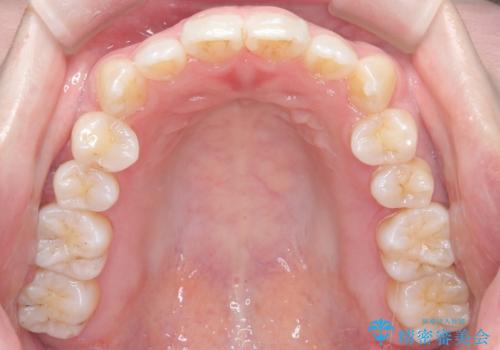

- 患者様は歯並びの乱れを気にされて来院されました。特に小臼歯の捻転(ねじれ)が強く、見た目だけでなく噛み合わせにも影響がありました。できるだけ目立たない方法を希望されていたため、インビザライン(マウスピース矯正)を基本としつつ、より精密な動きが必要な部分にはワイヤー矯正を併用する計画を立てました。また、小臼歯の捻転については**部分矯正(MTM:Minor Tooth Movement)**を取り入れ、効率的に改善を目指しました。

まず、全体の歯並びを整えるためにインビザラインを使用し、徐々に理想的な位置へと歯を移動させました。一方で、ねじれの強い小臼歯に対しては、**部分的なワイヤー矯正(MTM)**を行い、より精密なコントロールを実施。約2年の治療期間を経て、歯並びと噛み合わせが整い、見た目の美しさだけでなく、機能的な改善も達成しました。患者様からは「自然な仕上がりで、自信を持って笑えるようになった」と喜びの声をいただきました。